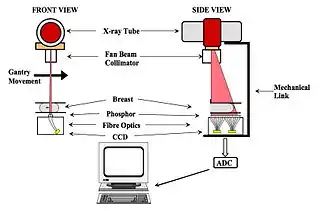

- Another alternative is to use a slot scanning arrangement - see Figure 7.24, panel (b). Here, X-rays transmitted through the compressed breast produce light in a strip of CsI:Tl phosphor and this light is collected by the fibre optics and conveyed to the CCD arrays. Some features of this design are:

- the image is acquired line by line by scanning the fan-shaped X-ray beam across the breast at a constant speed - see Figure 7.25. This form of image acquisition is analogous to the Scanned Projection Radiography image, also called Scout View, used in Computed Tomography (CT) scanning,

- Image acquisition time is 5 seconds, and

- Since the X-ray field-of-view and phosphor detector are relatively small, scatter does not represent a serious problem and grids do not need to be used - which represents a potential dose saving for patients.

- One of the disadvantages of the scanning slot approach is the necessity for long exposure times which increases the load on the X-ray tube. This can be addressed using a tungsten anode XRT, which has a substantially greater efficiency for X-ray production and heat dissipation than a tube with a molybdenum anode. The tube can operated between 20 and 45 kV with a choice of Al, Mo or Rh filters. This may seem counterproductive given the earlier discussion on the importance of using low kV in order to achieve high subject contrast. However, the detector has a dynamic range of 5,000:1 so that, while subject contrast is reduced, high image contrast can nevertheless be achieved.